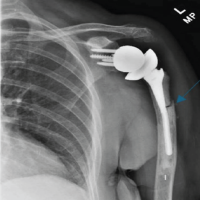

RTSA was performed under general anesthesia with an interscalene block for pain relief using the Comprehensive Reverse Shoulder System (Zimmer Biomet, Warsaw, Indiana, USA). The lesser and greater tuberosity fragments were mobilized, and no. 5 sutures (Ti-Cron, Medtronic, Minneapolis, Minnesota, USA) were placed at the bone-tendon interface to prevent comminution of the fragments. The glenoid baseplate and glenosphere were placed without difficulty despite soft glenoid bone. A distal cement restrictor was placed, and the implant was cemented into the humerus. Multiple variations of the glenoid tray and polyethylene components were used to create stability within the system construct. The tuberosities were secured to the humeral shaft using no. 5 sutures (Ti-Cron), which were placed before cementing (Fig. 2). No intraoperative complications were noted.

Figure 2: Anteroposterior radiograph taken after reverse total shoulder arthroplasty.